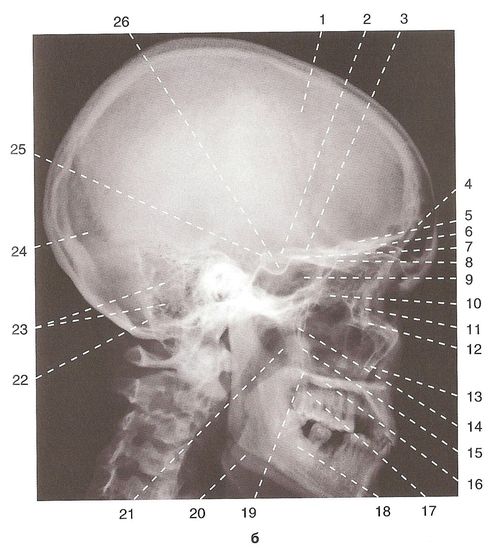

Анатомические изображения срединной сагиттальной линии черепа